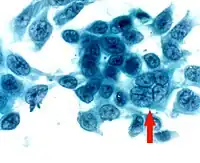

- Corneal smears or impression cytology specimens can be analyzed by culture, antigen detection, or fluorescent antibody testing. Tzanck smear, i.e.Papanicolaou staining of corneal smears, show multinucleated giant cells and intranuclear inclusion bodies, however, the test is low in sensitivity and specificity.